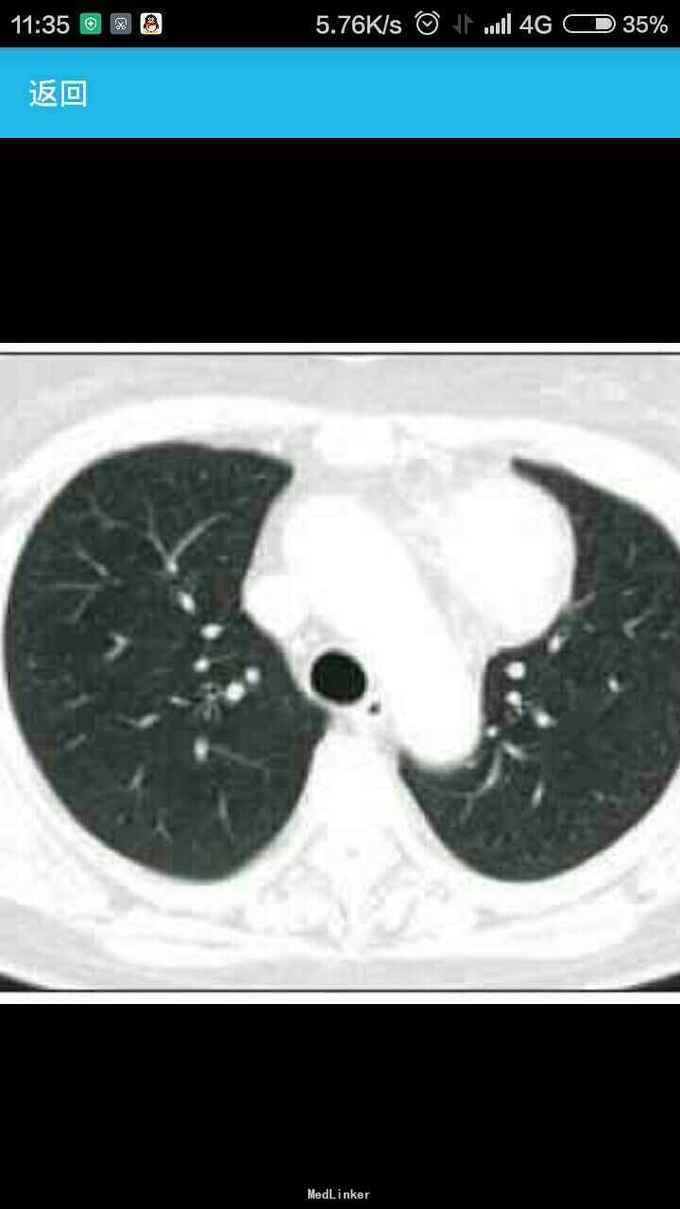

女性,60岁,因左 趾关节红肿、剧痛,红肿弥漫足背 23天来诊,不伴发热,无外伤史, 全身体检无明显异常。 胸片示,左侧前上纵隔占位性病变(图1)。胸部CT示,左侧前上纵隔内见5.7 cm×3.8 cm软组织肿块影,内见斑片状稍高密度影,境界不清(图2——5)。 实验室检查显示,血尿酸517.1 μmol/L(正常值180——357 μmol/L),临床诊断为“急性痛风”,为排除相关疾病作进一步检查。 印象:左侧前上纵隔占位(恶性肿瘤?畸胎瘤?)。 手术结果:肿瘤位于左前纵隔,大小约为8 cm×8 cm ×6 cm,质硬,表面光滑,与心包、无名静脉、肺门粘连(侵犯壁层、脏层、胸膜、肺门、心包、膈肌、膈神经,伴肿大淋巴结)。【病理结果示】(图6):肿块9 cm×6 cm×4 cm,侵犯周围脂肪组织,伴神经内分泌分化。肿块标记:CD5(+)、CD117(+)、嗜铬粒蛋白A(CgA)灶(+)、突触素(Syn,+)、CD56 (-)、细胞增殖因子Ki-67约20%(+)。【诊断】胸腺鳞状细胞癌Ⅱ——Ⅲ级,伴神经内分泌分化。